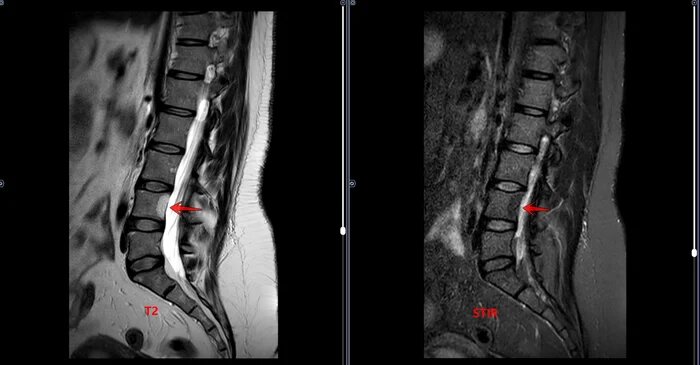

МРТ-Гемангиома тела L3 позвонка, очаг жировой дегенерации L4⁠⁠

В теле L3 позвонка определяется гемангиома, размером 15х14х14мм, без перифокальных изменений. В теле L4 позвонка определяется очаг жировой дегенерации костного мозга, размером 20х16х8мм.